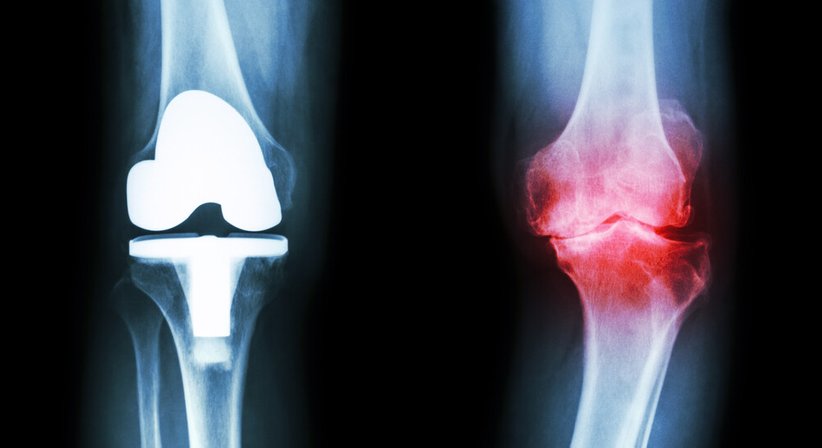

Bei einer Knieprothese handelt es sich um den Ersatz des verschlissenen Kniegelenks durch ein künstliches Gelenk – die Prothese ahmt die Form und Funktion des natürlichen Gelenks nach. Das Gelenk kann teilweise oder ganz ersetzt werden – je nachdem wird unterschieden zwischen einer Teilprothese (Schlittenprothese), durch welche ein Teil des Gelenks ersetzt wird, während das restliche Gelenk erhalten bleibt, und der Totalendoprothese, bei welcher das gesamte Gelenk entfernt und durch die Prothese ersetzt wird. Ob die Implantation einer Teilprothese ausreicht hängt ganz vom Einzelfall ab. Sie kommt beispielsweise bei Patienten in Frage, bei welchen alle Bänder erhalten und funktionsfähig sind und die Schädigung und Abnutzung des Gelenkknorpels nur einen Teil des Kniegelenks betrifft.